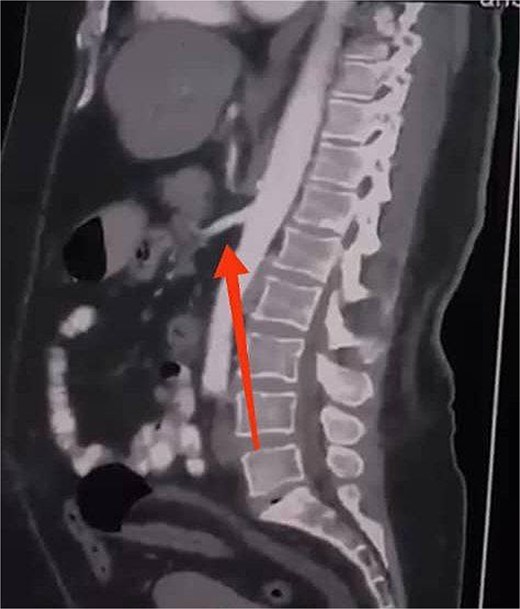

Initial imaging with a plain abdominal X-ray showed non-specific gas patterns without obstruction (Fig. 1). Contrast-enhanced CT revealed features of intestinal non-rotation, including abnormal duodenal positioning and atypical mesenteric vessel orientation. The sagittal view showed a retromesenteric duodenum without volvulus or bowel wall compromise (Fig. 2), while axial images demonstrated a reversed superior mesenteric artery (SMA)–superior mesenteric vein (SMV) relationship (Fig. 3), supporting malrotation. These findings are further illustrated in Supplementary Video S1), showing small bowel on the right, colon on the left, retromesenteric duodenum and abnormal SMA–SMV positioning. Colonoscopy showed normal mucosa without obstructive lesions.

Sagittal CT scan showing a retromesenteric course of the duodenum (indicated by an arrow).